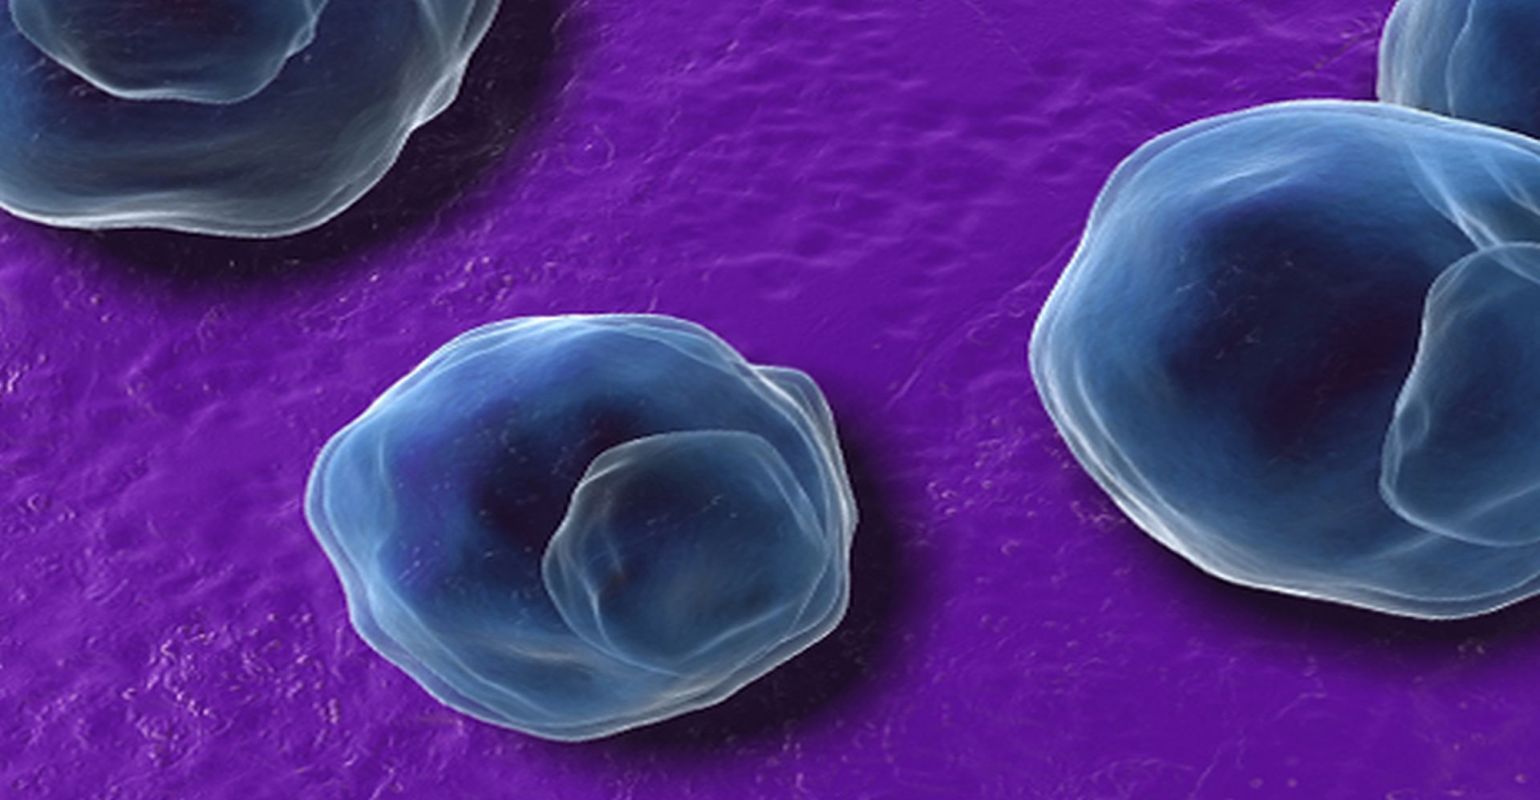

Фотографии бактерий, вызывающих бактериальные пневмонии у животных

Раздел: Другие животные